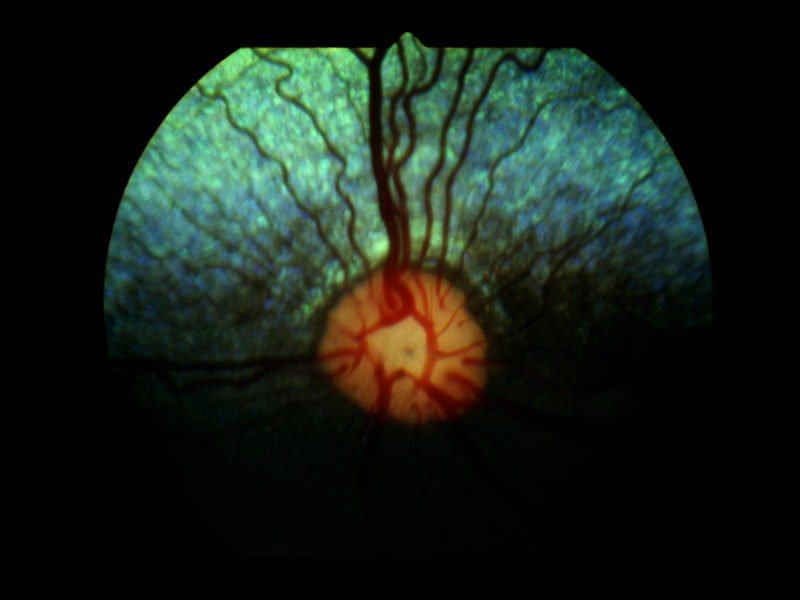

Bei der klassischen PRA beginnen die „Stäbchen“ die für das Nachtsehen zuständig zuerst zu degenerieren bzw. abzusterben. Dieser Vorgang ist nicht schmerzhaft. Im Anfangsstadium ist auffällig, dass sich die Tiere im Dämmerlicht oder im Dunkeln unsicher bewegen, ängstlich sind und unbekannte Objekte oder Personen verbellen. Teilweise stoßen die Tiere auch gegen ihnen unbekannte Dinge an oder weichen dem Besitzer nicht mehr von der Seite. Ein weiteres Zeichen ist der unvollständige Schluss der Pupillen bei einfallendem Licht und ein stärkeres “Leuchten” der Augen in der Dunkelheit als gewöhnlich, was ein Zeichen für eine dünner werdende Netzhaut ist. Dadurch kommt die unter der Netzhaut gelegene Schicht, das leuchtende Tapetum lucidum, verstärkt zum Vorschein. Diese Symptome verschlechtern sich dann in den darauffolgenden Monaten bis Jahren und führen zu einer spürbaren Sehverschlechterung auch im hellen Licht, da dann auch die „Zapfen“ beginnen zu degenerieren. Auch dieser Vorgang ist nicht schmerzhaft. Zwischen den ersten Symptomen und der vollständigen Erblindung vergehen in der Regel 3-6 Jahre.  Selten gibt es PRA Formen, bei welchen zuerst die Zapfen und im Anschluss daran die Stäbchen degenerieren. Dann tritt genau der umgekehrte Fall ein und die Tiere erblinden zuerst bei hellem Licht und anschließend auch bei Dunkelheit, dies sind Sonderformen und enden leider auch immer mit der vollständigen Erblindung des Tieres. Eine häufige Folgeerkrankung der PRA stellt der graue Star (Katarakt oder Eintrübung der Linse) dar. Als Folge des grauen Stars kann nach einigen Jahren der grüne Star (Erhöhung des Augeninnendrucks) auftreten. Der grüne Star gehört mit zu den schmerzhaftesten Erkrankungen des Auges und kann zum Verlust des gesamten Augapfels führen. Aus diesem Grunde sollten Tiere, die an der PRA erkranken, ca. einmal jährlich zu einer Kontrolluntersuchung der Augen vorgestellt werden, damit weitere Folgeschäden frühzeitig erkannt und dann behandelt werden können, um schmerzhafte Zustände zu vermeiden.

Ein auf Augenerkrankungen spezialisierter Tierarzt (Veterinär-Ophthalmologe) kann die Diagnose PRA anhand der typischen Symptome und der Befunde stellen, sobald die Erkrankung klinisch ausgebrochen ist, d.h. sobald auch nur geringe Anzeichen einer Sehschwäche auffällig werden. In Einzelfällen, in denen z.B. der graue Star die Sicht auf die Netzhaut verhindert, kann die Diagnose auch mit Hilfe eines Elektroretinogrammes (ERG) gestellt werden. Das ERG ist eine Untersuchung der Netzhautfunktionen, die mit einem EKG (Elektrokardiogramm) des Herzens verglichen werden kann.